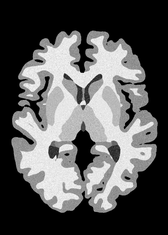

4.2 Registration to a 100 micron ex-vivo brain MRI volume

To showcase the efficacy of our method on real large scale images, we register a 250 in-vivo MRI image (Lüsebrink et al., 2017) to a 100 ex-vivo FLASH human brain volume (Edlow et al., 2019). This represents an inverse problem with more than 11.2B optimizable parameters (compared to 20M for clinical datasets), or 44.8GB of GPU memory. The entire problem does not fit on most GPUs, necessitating distributed multimodal registration. We optimize a composite transform - affine followed by a diffeomorphic mapping; details can be found in Section E.1. Multimodal deformable registration took 58 seconds on 8 NVIDIA A6000 GPUs, which is unprecedented at this resolution. Fig. 6 shows qualitative results, highlighting the ability to register highly detailed structures such as cerebellar white matter; these structures are not visible at macroscopic scales. The resultant advantages of performing registration at this scale can allow researchers to characterize the neuroanatomy at microscopic resolutions and allow morphometric analysis of cortical layers and subcortical nuclei among other structures.